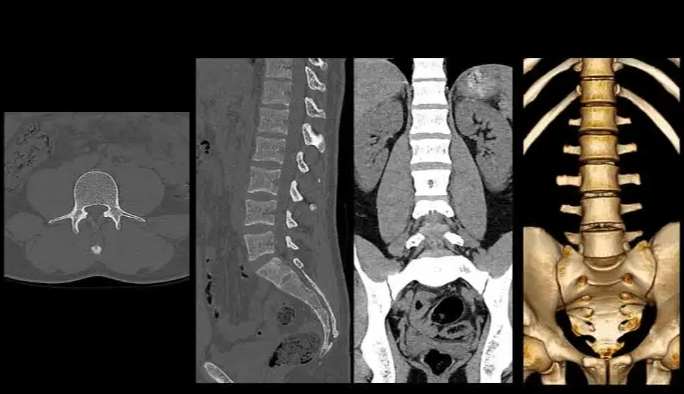

A reconstrução tridimensional (3D) é uma técnica avançada que transforma os cortes axiais obtidos durante a Tomografia Computadorizada (TC) em imagens volumétricas, permitindo uma visualização muito mais rica das estruturas anatômicas. Essa visualização pode ser manipulada em diversos ângulos, facilitando a interpretação por parte do médico radiologista e contribuindo para condutas clínicas e cirúrgicas mais seguras.

- MPR (Multiplanar Reconstruction): Visualização em planos axial, sagital e coronal

- VR (Volume Rendering): Reconstrução volumétrica realista, ideal para face, coluna e extremidades

- Aquisição com cortes finos (0.5 a 1.25 mm, de preferência)